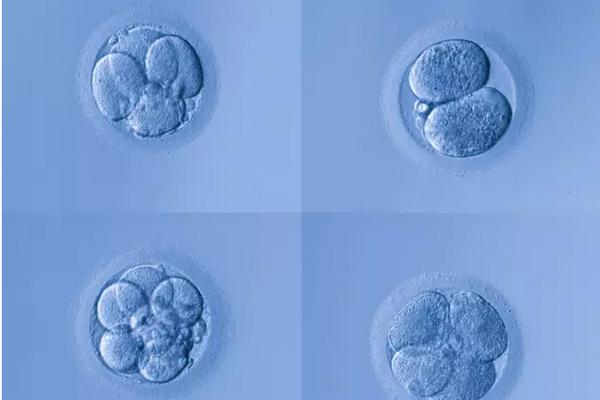

成功怀孕会经历以下几不同的阶段。- 精子必须到达并穿透并使女人的卵子受精。 - 产生的受精卵必须分裂并形成胚泡。 - 胚泡到达子宫并植入子宫内膜。 - 植入的胚泡...

胚胎培养技术是指在受精卵, 在体外条件下进行体外培养, 使其具有发育到2细胞胚胎乃至囊胚, 并具发育成一个孤立个体的潜能。传统的胚胎移植一般选择卵裂期胚胎但其多胎...

囊胚培养是精子与卵子结合为受精卵后继续在培养箱内培养5至6天,然后再进行移植或冷冻的方法。囊胚培养有哪些优点呢?能够筛选掉发育潜力差的胚胎早期的胚胎(受精后第二或...